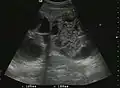

Hydatid liver cyst. Diagnostic criteria are the presence of membranes and sediment inside.